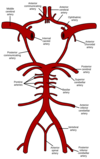

Course of Cerebral Arteries

ICA & VA pierce the dura and course in the subarachnoid space along with their branches. These branches penetrate into the brain parenchyma and as they do are surrounded by the tapered perivascular space (Virchow-Robbin) and the pia mater or BBB.

What are the primary blood supply to the brain

Internal Carotid (80%) - anterior circulation

Vertebrabasilar Arteries (20%) - posterior circulation

Branches of Internal Carotid Artery

- Opthalmic Artery

- Posterior Communicating Artery (PCoA)

- Anterior Cerebral Artery (ACA)

- Anterior Communicating Artery (ACoA)

- Middle Cerebral Artery (MCA)

- Anterior Choroidal Artery

Branches of Vertebral Arteries

Posterior Inferior Cerebral Artery (PICA)

Anterior Spinal Arteries

Branches of Basilar Artery

Anterior Inferior Cerebellar Artery (AICA)

Superior Cerebellar Artery

Posterior Cerebral Artery

Pontine Arteries

What arteries contribute to the Circle of Willis

- Internal Carotid A

- Anterior Cerebral A.

- Anterior Communicating A.

- Posterior Communicating A.

- Posterior Cerebral A.

Termination of the ICA, VA and the circle of Willis are located where

Subarachnoid space